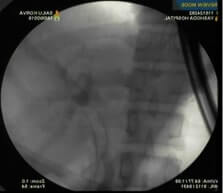

X ray showing biliary SEMS

Diagnosis and treatment: On side viewing endoscopy, large mass lesion seen infiltrating the ampulla and periampullary region was seen. Biopsy from mass lesion revealed poorly differentiated adenocarcinoma. In view of cholangitis, biliary drainage by ERCP (Endoscopic Retrograde Cholangiopancreatography) was tried. However, biliary access was not feasible because of duodenal luminal narrowing and diffuse infiltration. Subsequently, EUS (Endosonography) guided choledochoduodenostomy from first part of duodenum was done and fully covered biliary metallic stent was placed. The procedure was uneventful and patient fever and jaundice subsided. On follow up visit, bilirubin was in normal range, and the patient was planned for chemoradiation due to locally advanced tumor.